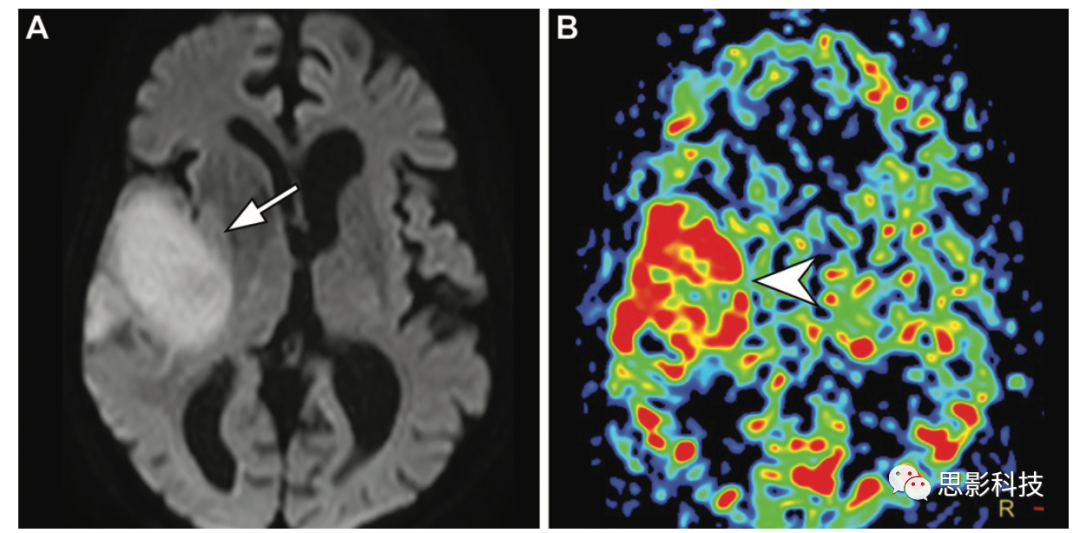

16 一例53歲女性在晚期高級(jí)別膠質(zhì)瘤術(shù)后影像隨訪時(shí)殘留或復(fù)發(fā)腫瘤。(A,B)軸位彌散加權(quán)(A)和高空間分辨率增強(qiáng)T1加權(quán)(B)顯示不均勻強(qiáng)化和沿手術(shù)腔后緣的受限擴(kuò)散(箭頭),沿后內(nèi)側(cè)邊緣有結(jié)節(jié)狀和不規(guī)則的局灶增厚。

(C)ASL MR圖像顯示外科手術(shù)腔后內(nèi)側(cè)緣高CBF,伴有局灶結(jié)節(jié)增厚(箭頭),表明存在復(fù)發(fā)或殘留腫瘤。